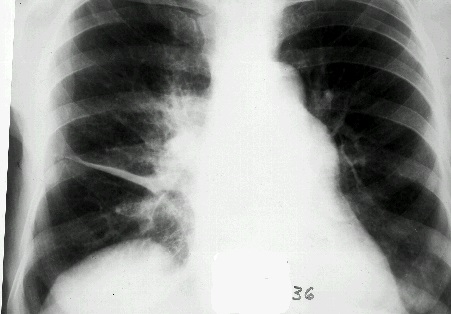

Наряду с клиническими проявлениями экссудативного плеврита при осмотре пациента выявляется асимметрия грудной клетки, выбухание межреберных промежутков на соответствующей половине грудной клетки, отставание пораженной стороны при дыхании. Перкуторный звук над экссудатом притуплен, бронхофония и голосовое дрожание ослаблены, дыхание слабое или не выслушивается. Верхняя граница выпота определяется перкуторно, при рентгенографии легких или при помощи УЗИ плевральной полости.